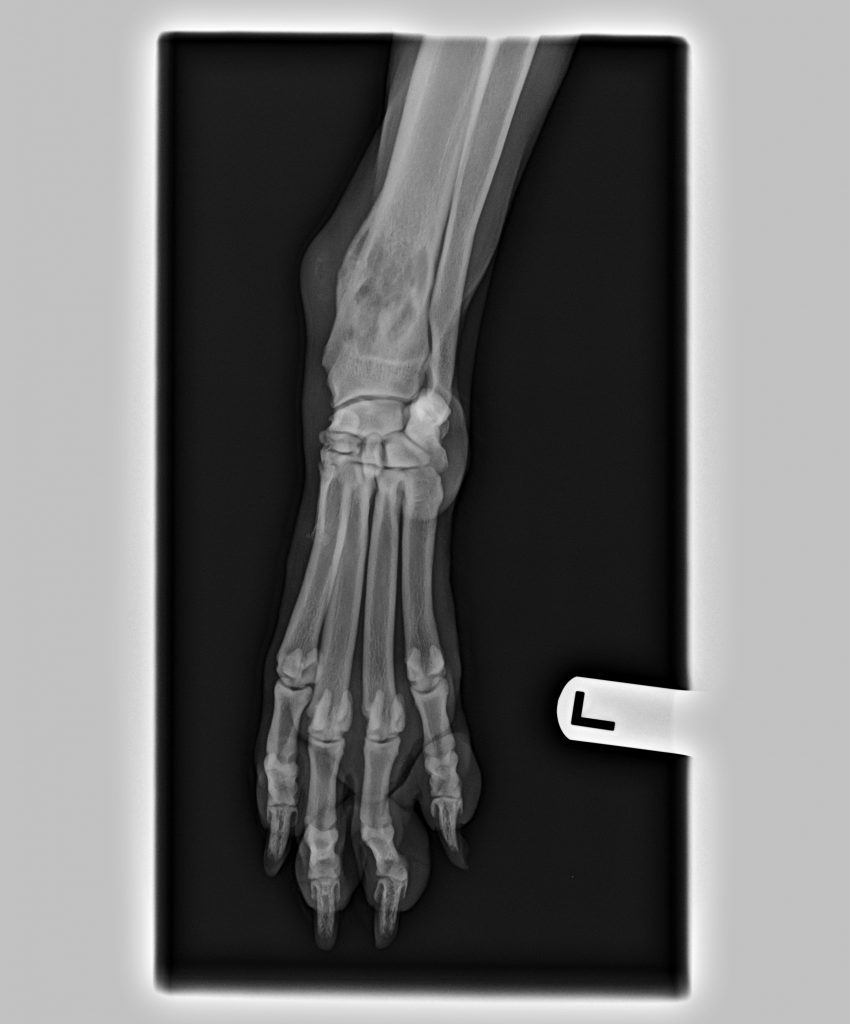

Paciente canino de la raza doberman, macho castrado de 14 meses de edad. Se presenta en consulta después de una cojera intermitente con apoyo de peso, del miembro anterior izquierdo. Presenta dolor y algo de inflamación de consistencia dura en la zona de su radio distal. El dueño ha probado 5 días de carprofeno sin que el perro parezca mejorar su sintomatología por lo que se realizan radiografías de la lesión (FOTO) y posteriormente una punción con aguja de 18G bajo sedación de la lesión ósea (FOTO)

¿Con la anamnesis, tipo de lesión ósea y citología, cual es el diagnóstico de este paciente?